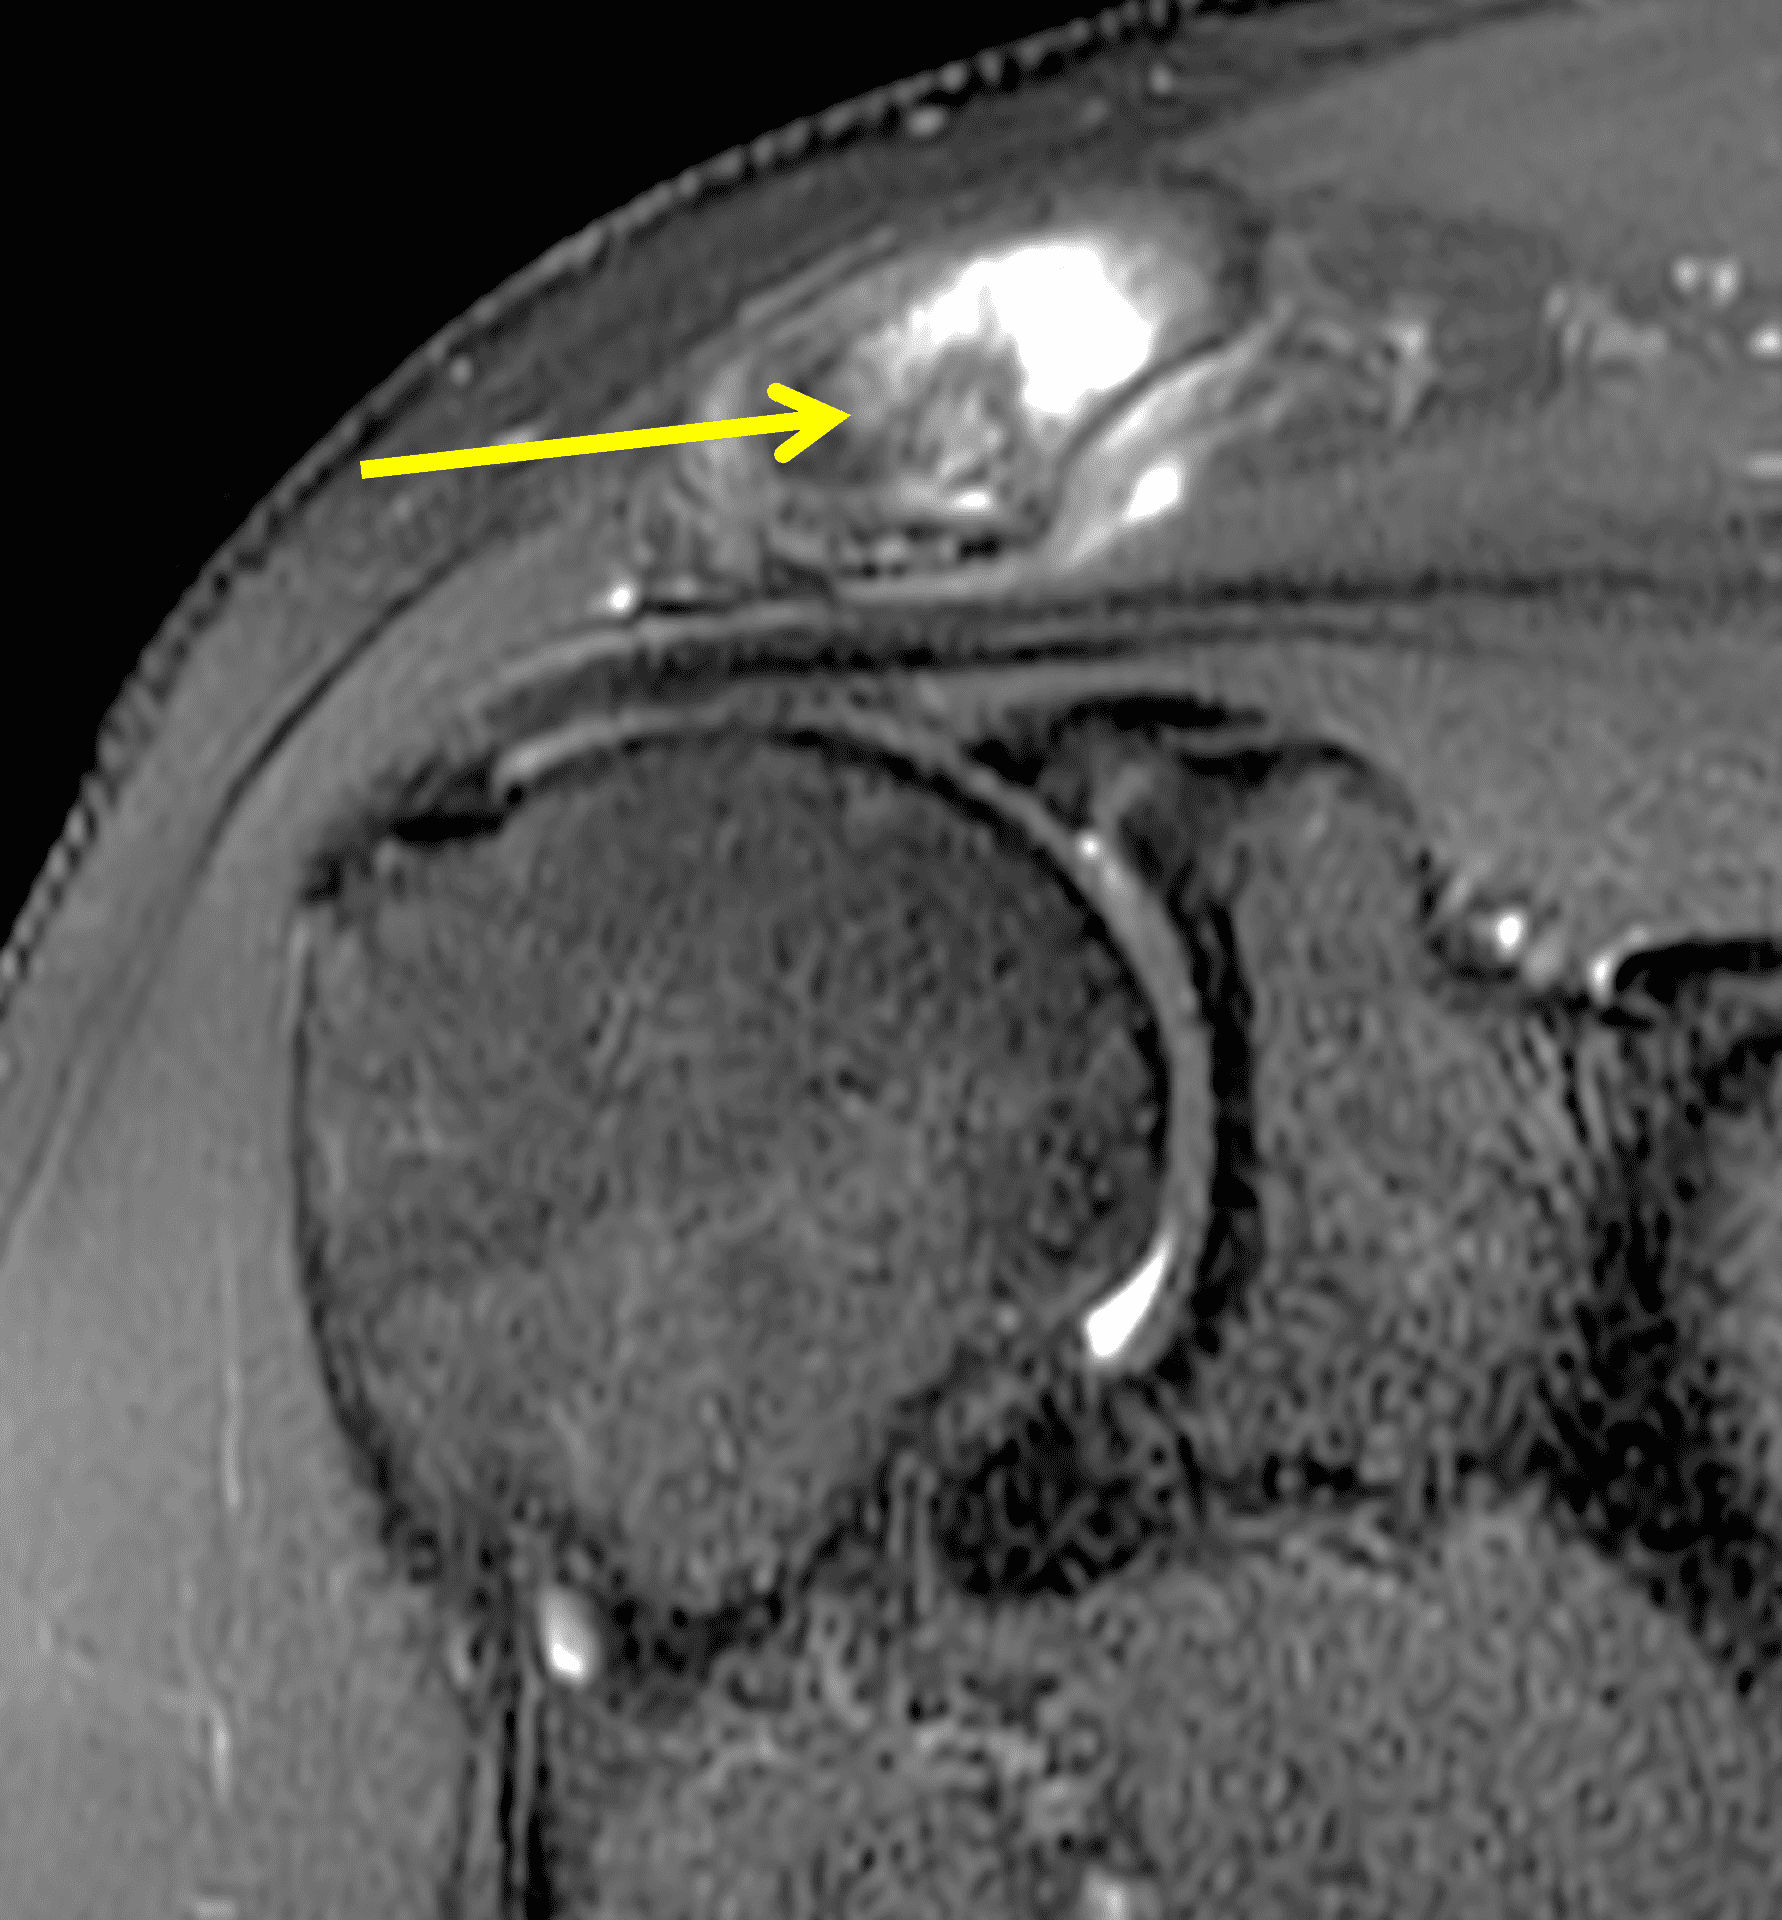

A 49-year-old male, avid weightlifter complains of chronic pain along the superior aspect of his right shoulder. He denies acute trauma. An AP radiograph (Figure 1A), as well as oblique coronal SPAIR (Figure 1B), axial fat-suppressed fluid sensitive (Figure 1C), and oblique sagittal T2-weighted images (Figure 1D) are shown. What are the findings? What is your diagnosis?

MRI: MRI is the primary imaging modality used for the diagnosis of DCO and identifies relevant findings earlier than radiographs or CT.  To differentiate DCO from similar conditions, it is important to identify underlying findings that are isolated to or more pronounced in the distal clavicle compared to other structures.  Osseous changes along both the acromial and distal clavicular margins of the joint often point to a different diagnosis.2

The principle MRI finding of DCO is distal clavicular marrow edema and surrounding inflammation on fluid-sensitive pulse sequences, especially with fat suppression (Figures 3 and 4).2, 9 Marrow changes can occur in patients with normal radiographs,10 in which case a term like “stress/overuse related marrow edema,” might be preferable to “osteolysis.” On MRI, more severe cases may show erosions or cysts in the distal clavicle and loss of the subchondral bone plate in addition to more pronounced marrow and soft tissue edema. A band of low signal paralleling the distal bone end may be present, suggesting a stress fracture line (Figure 5).8 However, a similar appearance can be due to the sclerotic rim surrounding distal clavicle cysts or small erosions (Figure 6). A small effusion or mild synovitis is often present in the AC joint.  Soft tissue edema within and surrounding the AC joint capsule and distal clavicular periosteum may be visible (Figure 3).  Some patients may also show marrow edema (or even erosions) in the anterior acromion, but the changes are typically more severe in the distal clavicle (Figures 5 and 7).2